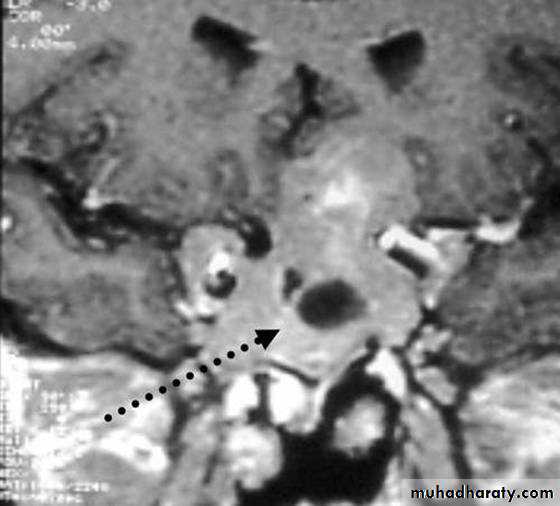

4- Inferior petrosal sinus sampling;

Catheters placed in both inferior petrosal sinuses and simultaneous sampling from these and peripheral blood for ACTH.

> 200% compared to peripheral ACTH, suggests pituitary-dependent disease.

< 150% suggests ectopic ACTH syndrome.

The test is usually performed by vascular radiologists on an outpatient basis. With local anesthesia, femoral catheters are advanced bilaterally up to the inferior petrosal sinuses. After confirmation of catheter location by fluoroscopy, several ACTH samples are drawn simultaneously from the right and left at the same time that a peripheral level is being drawn from an arm vein. CRH can also be injected to provoke ACTH release. Samples are then assayed for ACTH, and the pituitary-to-peripheral ratios are calculated.